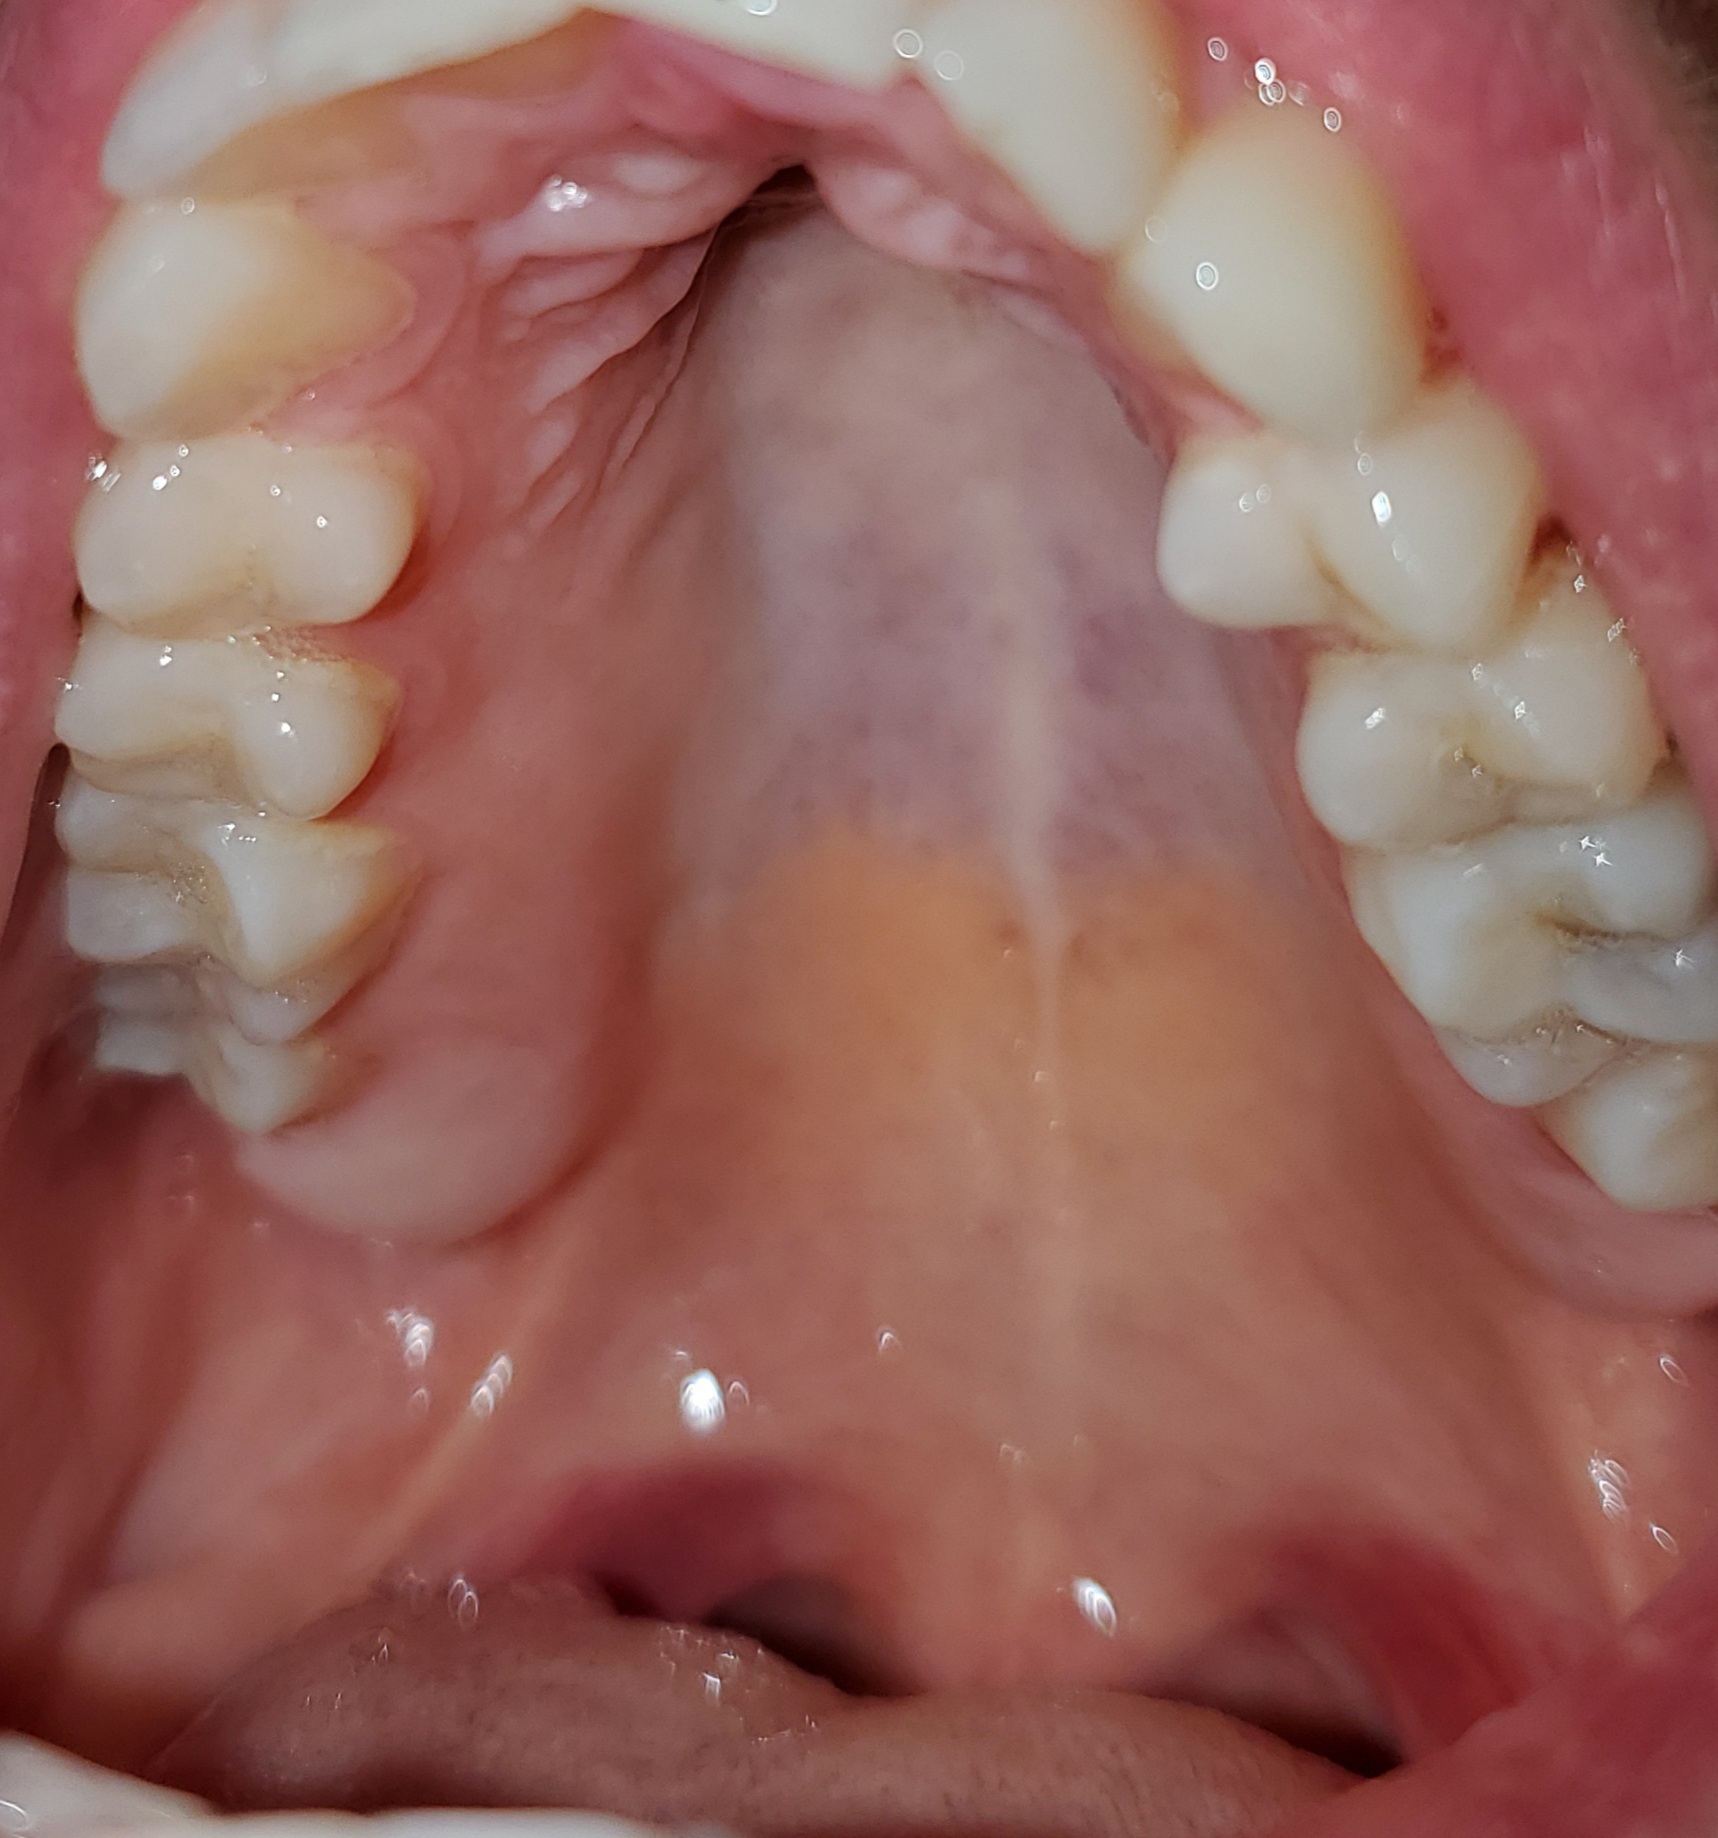

Domande di Dentisti-Italia.it | Pag. 85 (da 46 a 50)